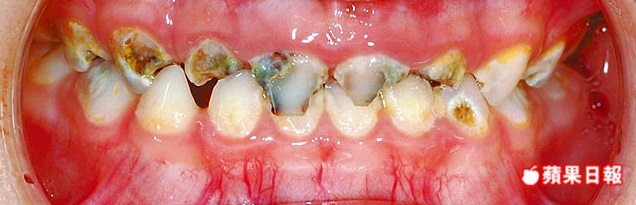

▲ 蛀牙常導致牙齦與口腔疼痛不適。

蛀牙未處理,也會影響美觀。